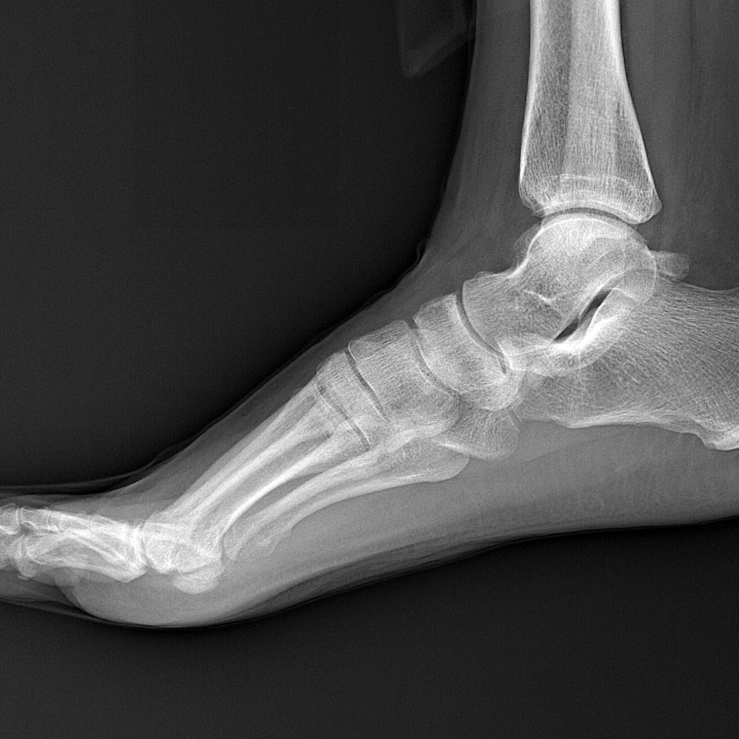

患者: 女性,45岁 -

初诊日期: 2025年1月25日

患者主诉其右踝于2024年12月15日下楼梯时摔倒受伤,随后进行了石膏固定,并一直采取保守治疗至今。目前使用拐杖+行走靴辅助行走,下台阶时外踝疼痛。 -

踝关节及第一跖趾关节 (1st MTR) 活动度受限,患者抗拒跖屈。

触诊: 足底筋膜紧张;小腿三头肌萎缩伴胫骨后肌压痛;跟骨和距骨活动受限。